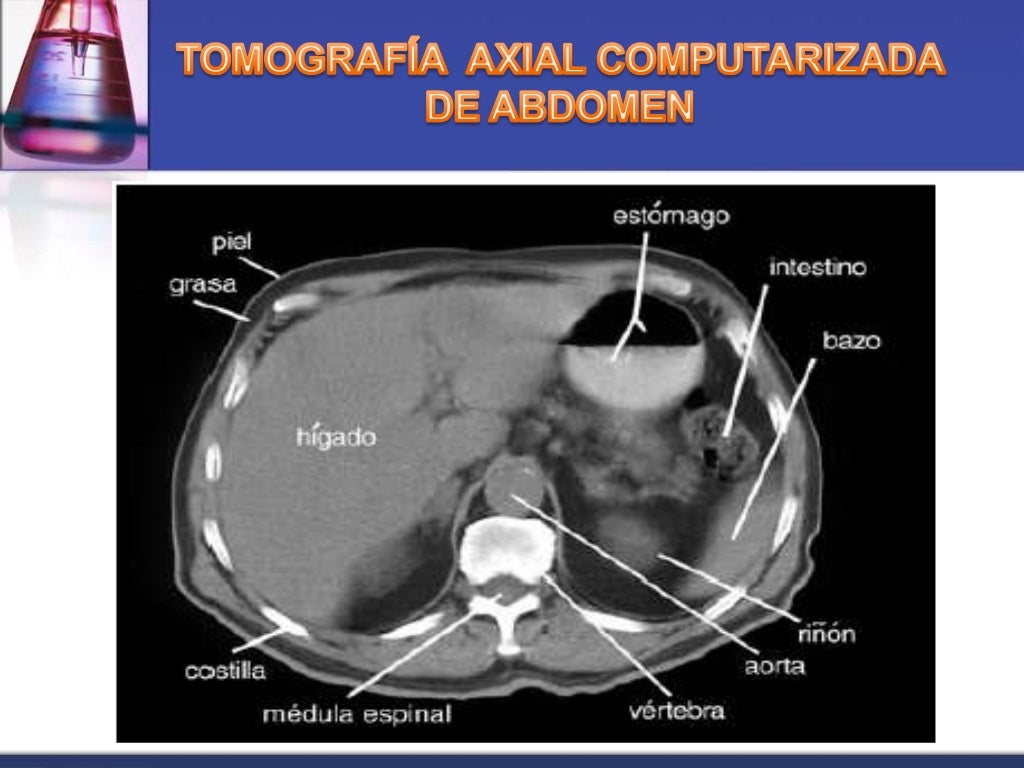

que es una tomografia abdominal La tomografía computarizada, más comunmente conocida como exploración por tc o tac, es un examen médico de diagnóstico por imágenes. La angiotomografía computarizada del corazón es una forma útil de detectar arterias coronarias obstruidas. Una tomografía computada abdominal utiliza una máquina especial de rayos x para tomar imágenes del hígado, bazo, riñones, vejiga, estómago, intestinos, páncreas y glándulas. Una tomografía de abdomen es un estudio de imagen que ayuda a detectar problemas de salud en el área del abdomen. Una tomografía computada abdominal utiliza una máquina especial de rayos x para tomar imágenes del hígado, bazo, riñones,. La tomografía computarizada, tc, es un procedimiento con imágenes que usa equipo especial de rayos x para crear imágenes detalladas, o exploraciones, de regiones. Al igual que los rayos x. La angiotomografía computarizada podría costar menos que una.